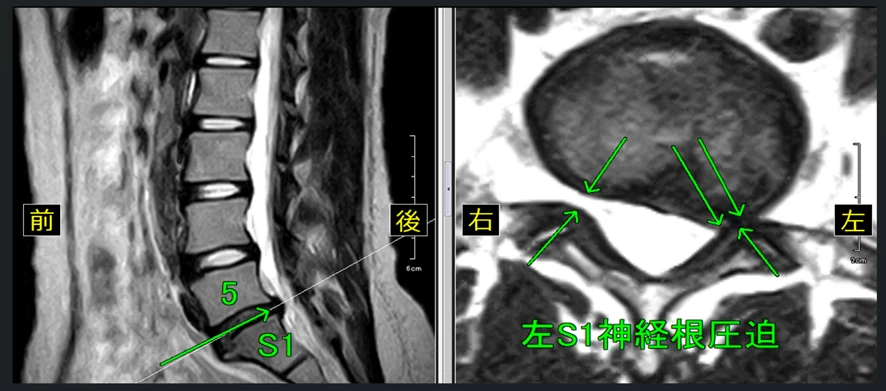

【12級レベルの腰椎のMRI画像】

※腰椎椎間板の大きな膨隆が認められるとともに右神経根の圧迫が認められます。